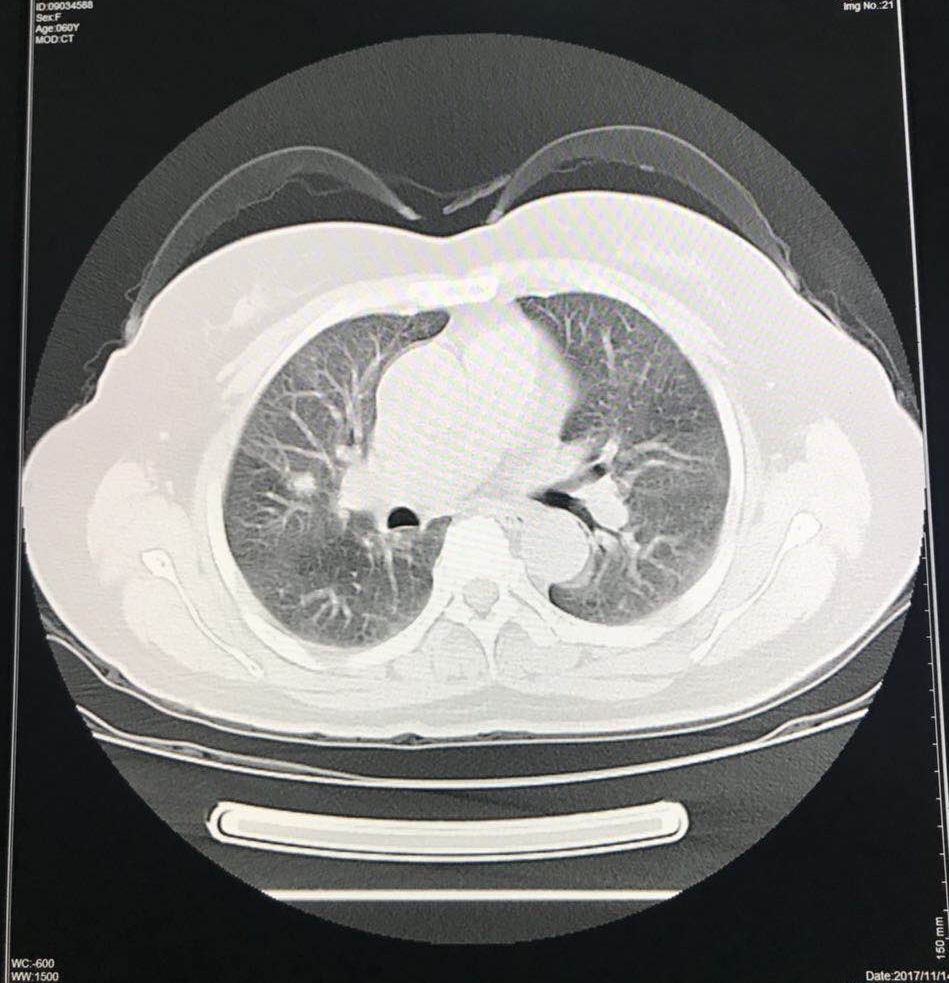

2程化疗后CT评估:两侧盆腔髂总动脉旁,腹主动脉旁及左锁骨上、纵膈、右肺门多发淋巴结转移、较前缩小。两肺多发转移瘤、较前增大。

2程化疗后CT:两侧盆腔髂总动脉旁、腹主动脉胖淋巴结肿大,较大约2.2×1.8cm,较前缩小;左锁骨上、纵膈、右肺门多发小淋巴结,最大0.8cm,较前略缩小。

两肺多发转移瘤,左下肺最大约1.4cm,较前缩小。